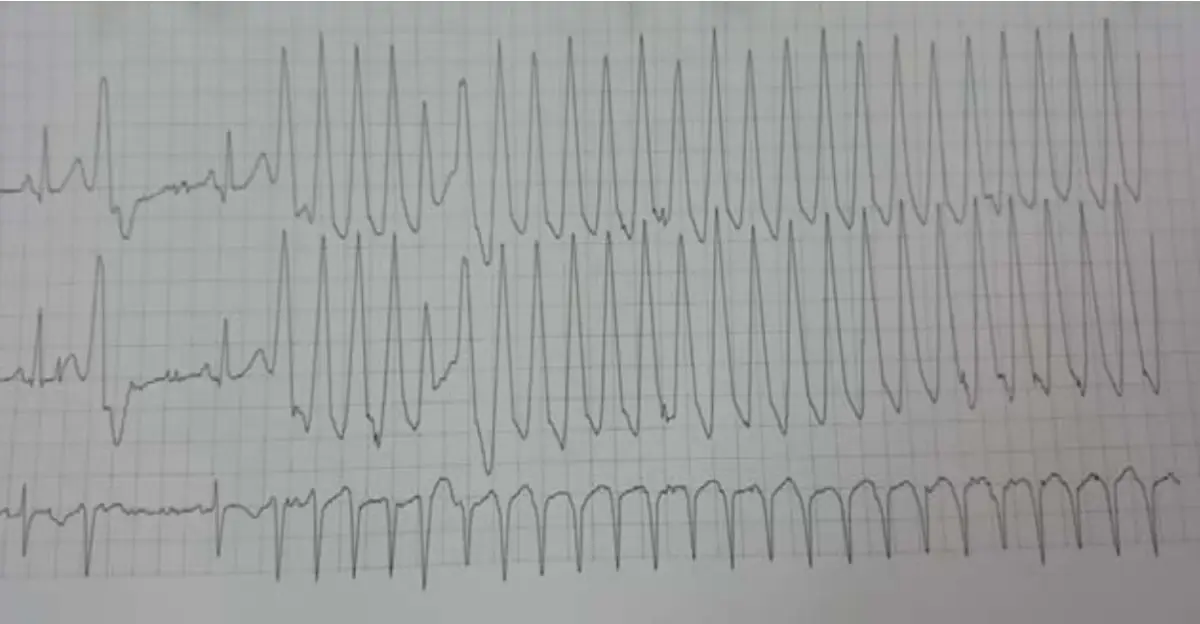

病人是位47歲家庭主婦,自7歲起就診斷有心臟病,18歲懷孕生有一子,過程尚稱順利,近十年來偶有心悸及胸悶,近二年曾有五次昏厥,因此住院。理學檢查及生化檢驗都正常。胸X光及心電圖(如圖)。本病人最有可能的診斷是:

本題考察心律不整的鑑別診斷,尤其是寬QRS波心搏過速(wide QRS complex tachycardia)的判讀。病人為47歲女性,自幼(7歲)即有心臟病史,近十年有心悸及胸悶,近二年有五次昏厥(syncope)。理學檢查與生化檢驗正常,搭配胸部X光與心電圖(含正常竇性心律與心搏過速發作時)進行診斷。正確答案為 (D) 來自右心室流出道的單形性心室頻脈(Monomorphic ventricular tachycardia from outflow tract,RVOT VT)。

影像分析:

圖一(胸部X光,PA view): 胸部後前位X光顯示心臟輪廓正常大小,肺野清晰,無肺水腫、肺充血或肺炎浸潤。無明顯心臟結構異常跡象。此發現與「理學檢查及生化檢驗都正常」相符,提示此心臟病可能並非結構性心臟疾病(structural heart disease),而是功能性心律不整。

圖二(12導程心電圖,竇性心律): 12導程心電圖顯示正常竇性心律,心率規則,QRS波形正常,無預激波(delta wave),排除 WPW syndrome。PR間期正常,QT/QTc間期在正常範圍內,排除 Long QT syndrome。此「正常基礎心電圖」是重要的鑑別診斷線索——若基礎ECG正常,更傾向idiopathic RVOT VT而非L